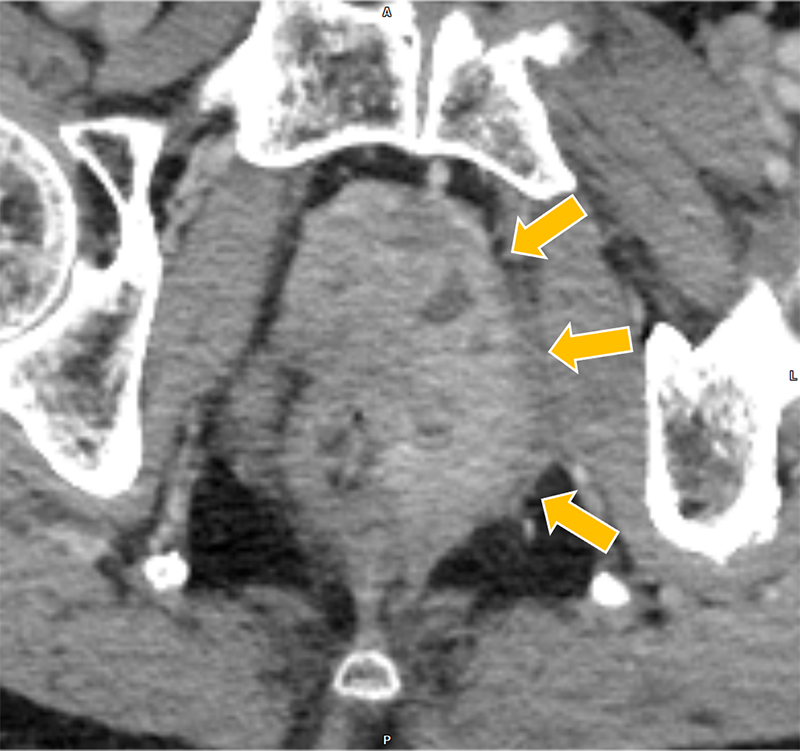

膀胱癌の治療経過観察中、胆嚢癌が疑われ、術前精査目的に肝ダイナミックCTが施行された。胆嚢底部に長径30mm程の腫瘤を認めた。また、胆嚢左側や背側にリンパ節転移を疑う造影結節を認めた。さらに、同CTで前立腺左葉から直腸左側にかけての膿瘍形成が指摘され、後の精査でBCG注入療法に伴う骨盤内BCG感染症が明らかとなった。膿瘍の治療過程で腹膜播種が出現、胆嚢癌は化学療法の方針となった。